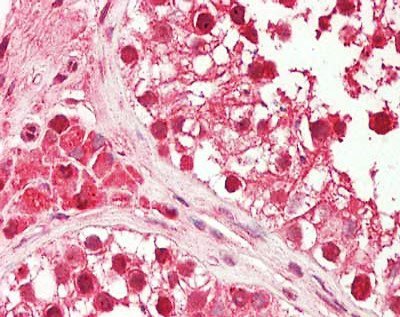

免疫组织化学(IHC)组织样本分析(图2-4)对于检测样本中的蛋白质至关重要,通常用于诊断实验,但不会产生允许共定位实验的图像。

IHC

组织标本用福尔马林固定石蜡包埋固定。蛋白检测采用一抗5µg/mL (HDAC5和HDAC10)或1:500 (HDAC1)室温1 h。二抗:过氧化物酶兔二抗(Rockland, p/n 611-103-122),室温1:10 000孵育45分钟。用苏木精紫或蓝核复染显示蛋白为红色或紫色信号。一抗显示:HDAC1 (Rockland, p/n 600-401-879), HDAC5 (Rockland, p/n 600-401-J69)和HDAC10 (Rockland, p/n 600-401-J75)。

在这里,我们展示了HDAC1在癌组织(图2)和表皮样癌细胞(图5)中的染色。在分析的样本中,HDAC1定位被确认为细胞核。在某些肿瘤样本中未观察到报道的HDAC1的胞浆染色。使用发生的与共焦成像相比,显微镜显示分辨率明显提高(图5)。这些结果清楚地表明,使用适当的经验证抗体和发生的显微镜是研究超越衍射极限的亚细胞结构的重要工具,它可以纠正定义不清的图像。这在细胞内蛋白质共定位研究中至关重要。